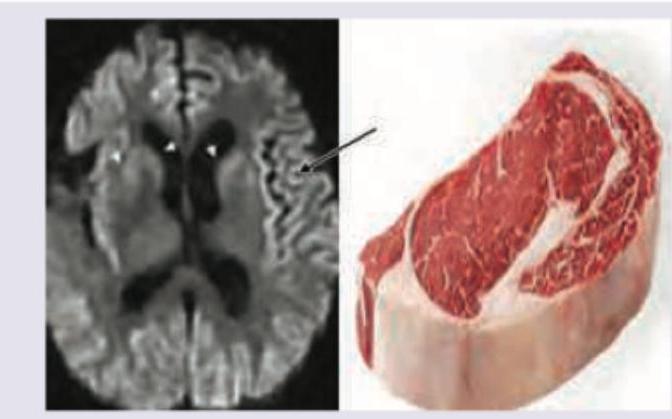

A 25-year-old abattoir worker presents with myoclonus and amnesia for recent and remote events for last 1 year. MRI head was performed. All statements are correct about the organisms leading to this disease except:

Explanation: ***Sensitive to ethylene dioxide*** - Prions, the causative agents of Creutzfeldt-Jakob Disease (CJD), are **resistant to conventional sterilization methods**, including ethylene oxide, radiation, and disinfectants like formaldehyde. This statement is incorrect. - They are primarily inactivated by methods that denature proteins, such as **autoclaving at high temperatures and pressures** or strong sodium hydroxide solutions. *Absence of nucleic acid* - **Prions are infectious proteinaceous particles** that lack nucleic acid (DNA or RNA), which distinguishes them from viruses, bacteria, and other conventional pathogens. - They propagate by inducing conformational changes in normal host proteins. *CSF examination of patient shows presence of protein 14.3.3* - The presence of **14-3-3 protein** in cerebrospinal fluid (CSF) is a significant and widely used diagnostic marker for **Creutzfeldt-Jakob Disease (CJD)**. - Elevated levels of this protein indicate neuronal damage and are often found in patients with rapidly progressive dementia caused by prions. *MRI shows cortical ribboning* - **Cortical ribboning**, characterized by hyperintense signal changes in the cerebral cortex on diffusion-weighted imaging (DWI) and fluid-attenuated inversion recovery (FLAIR) sequences, is a **highly characteristic finding in MRI scans of patients with CJD**. - This MRI finding, along with involvement of the basal ganglia and thalamus, supports the diagnosis of CJD.